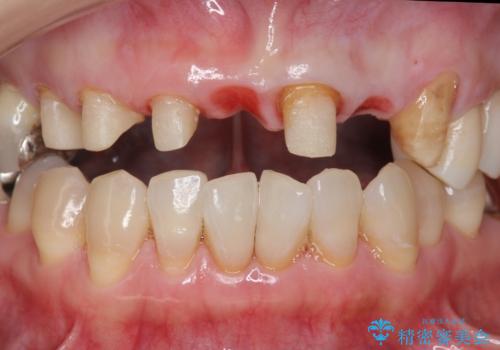

ブリッジの支台歯は、根の再治療を含めて行なっています。

下の歯は、患者様の希望によりホワイトニングを行なっています。

根の治療からやり直して新しいブリッジにしています。